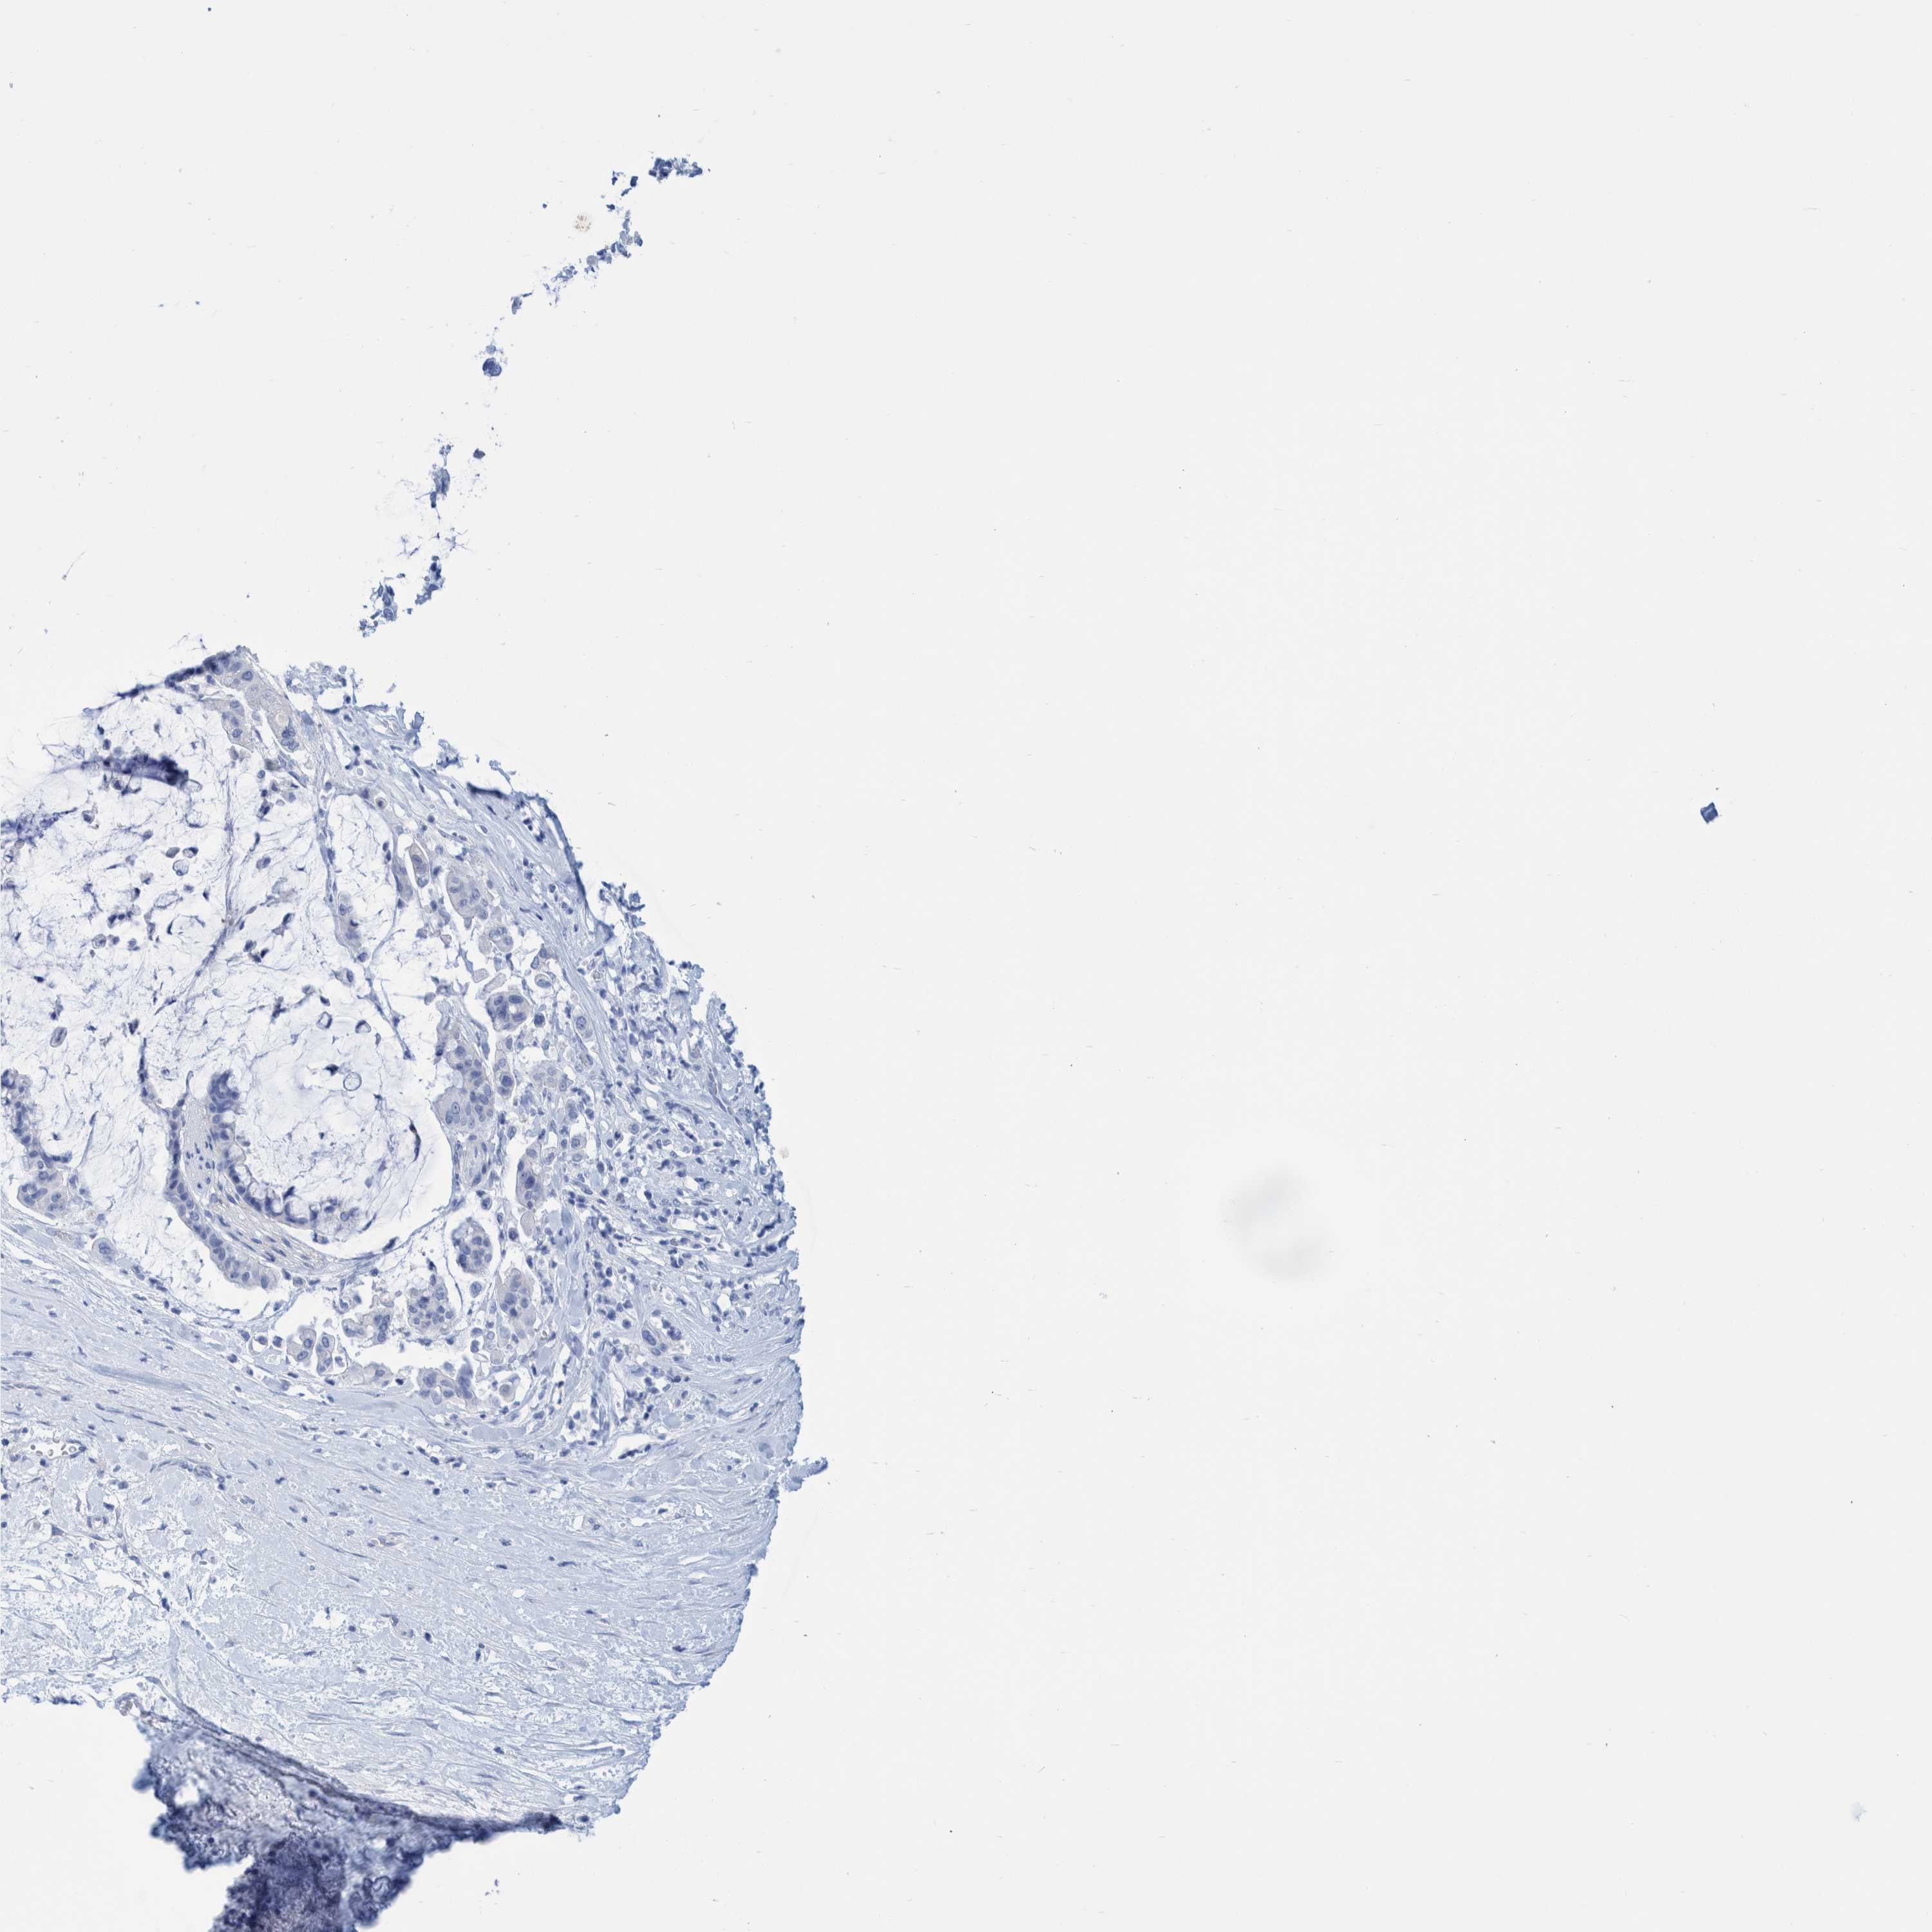

PANCREATIC CANCER - Protein expressioni

A mouse-over function shows sample information and annotation data. Click on an image to view it in a full screen mode. Samples can be filtered based on level of antibody staining by selecting one or several of the following categories: high, medium, low and not detected. The assay and annotation is described here.

Note that samples used for immunohistochemistry by the Human Protein Atlas do not correspond to samples in the TCGA dataset.

Antibody stainingi

Antibody staining in the annotated cell types in the current human tissue is reported as not detected, low, medium, or high, based on conventional immunohistochemistry profiling in selected tissues. This score is based on the combination of the staining intensity and fraction of stained cells.

Each image is clickable and will lead to virtual microscopy that enables deeper exploration of all samples and also displays staining intensity scores, fraction scores and subcellular localization as well as patient and tissue information for each sample.

Antibody HPA022269

Staining

High

Medium

Low

Not detected

Intensity

Strong

Moderate

Weak

Negative

Quantity

>75%

75%-25%

<25%

None

Location

Nuclear

Cytoplasmic/membranous

Cytoplasmic/membranous,nuclear

Adenocarcinoma, NOS